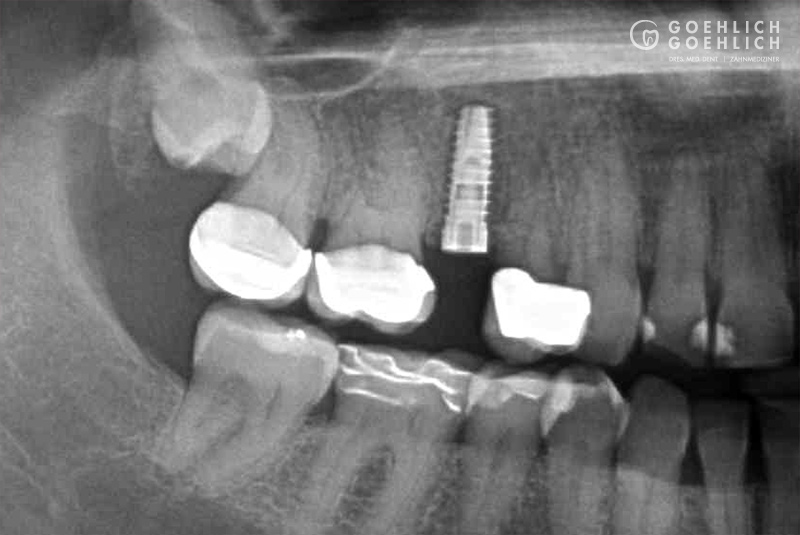

Als Implantat bezeichnet man in der Zahnmedizin eine künstliche Zahnwurzel, die nach Verlust eines eigenen Zahnes als Ersatz eingebracht wird. Das Implantat dient als Basis bzw. Verankerung einer festsitzenden Krone. Geht nur ein Zahn verloren, dient das Implantat zum Schluss der Lücke, ohne dass eine Brücke angefertigt werden muss und dafür die vielleicht intakten Nachbarzähne abgeschliffen werden. Damit schonen wir die umgebenden Zähne. Spätfolgen des Zahnverlustes, wie Kiefergelenkprobleme, Zahnwanderungen oder Karies können vermieden werden. Sind bereits mehrere Zähne verloren gegangen, die nur durch eine Teil- oder Vollprothese ersetzt werden können, ermöglichen wir durch das Einbringen mehrerer Implantate wieder einen festsitzenden Zahnersatz.

Mittels digitaler Volumentomographie (DVT) sind wir in der Lage, die knöcherne Ausgangslage vor Implantation dreidimensional darzustellen. So können die genauen Lagebeziehungen zu Nerven oder auch zur Kieferhöhle optimal bestimmt werden.

Implantate bestehen aus dem körperverträglichen und langlebigen Metall Titan. In einem minimalinvasiven operativen Eingriff setzen wir das Implantat in den Knochen ein. Die speziell bearbeitete Oberfläche garantiert ein zügiges Einheilen und das feste Verwachsen mit dem umgebenden Knochengewebe. Implantate können darüber hinaus den gefürchteten Knochenschwund in zahnlosen Kieferabschnitten verhindern oder verzögern. Den eigenen Zahnwurzeln ähnlich, übertragen Implantate die Kaukräfte auf den Kieferknochen. Dieser Trainingseffekt ist ein wichtiger Reiz für den Erhalt des Knochen- und Stützgewebes. Deshalb sollten Implantate möglichst bald nach dem Verlust oder Entfernen eines Zahns verankert werden.